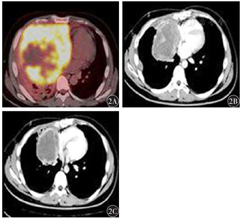

患者,男性,26岁。2020年5月出现咳嗽、胸闷、肩背部疼痛,6月19日就诊于我院。PET-CT示:右侧胸前恶性占位,大小为16.7 cm×15.1 cm×22.3 cm,右侧胸膜及纵隔多发淋巴结转移。肿瘤标志物:甲胎蛋白(AFP)36 343 ng/ml,β人绒毛膜促性腺激素(β-HCG)<2.0 mU/ml。2020年6月20日行CT引导下胸部肿块穿刺活组织检查,病理结果示:卵黄囊瘤。免疫组织化学:AFP、CK阳性,Ki-67阳性指数为50%。2020年6月开始行姑息一线第1~4个周期ABX+EP方案化疗:白蛋白结合型紫杉醇125 mg/m2 ,第1、8天;依托泊苷100 mg/m2,第1天至第5天;顺铂20 mg/m2,第1天至第5天;每3周重复。4个周期后影像学评价为部分缓解(PR),AFP 3 084 ng/ml。2020年10月于胸外科行纵隔肿物姑息性切除术,术后病理诊断为卵黄囊瘤(图1)。免疫组织化学:AFP、CK、PLAP、SALL4阳性,CD117、OCT-4阴性,Ki-67阳性指数为50%。因上腔静脉血栓,每日口服利伐沙班片(拜瑞妥)10 mg,每日1次。2020年11月(术后1个月)出现疾病进展(PD),AFP 54 678 ng/ml。因既往化疗有效,2020年11月至2021年1月行第5~7个周期ABX+EP方案化疗,剂量同前。同时加用安罗替尼12 mg/d,第1天至第14天口服,每3周重复。患者治疗7个周期后影像学检查评价疗效为PR(图2),AFP 3 955 ng/ml。2021年1月因纳差、消瘦要求暂停静脉注射化疗,仅口服安罗替尼,剂量同前。安罗替尼口服过程中,未出现骨髓抑制、肝肾功能损害、高血压及出血等不良反应。2021年3月复查提示PD,AFP 46 869 ng/ml。于3月30日开始安罗替尼+TIP方案治疗:安罗替尼12 mg/d,第1天至第14天口服;白蛋白结合型紫杉醇125 mg/m2,第1、8天;异环磷酰胺1.8 g/m2,第1天至第4天;顺铂20 mg/m2 ,第1天至第4天;每3周重复,共2个周期,疗效评价为PR,AFP 5 155 ng/ml。后因个人原因要求再次停止静脉注射化学治疗。5月27日至7月2日行局部放疗,以右前纵隔占位为肿瘤体积,照射剂量5 000 cGy,25次,共5周。放疗期间同期口服安罗替尼,剂量同前。8月10日出现额叶大面积脑出血及昏迷,安罗替尼已停药4 d,当天测得凝血酶原时间(PT)17.5 s,活化部分凝血活酶时间(APTT)35.5 s,D-二聚体4.97 s,考虑利伐沙班片致脑出血可能性大,不排除与安罗替尼相关,予停用利伐沙班片,转入神经外科治疗,于2021年9月死于呼吸衰竭。